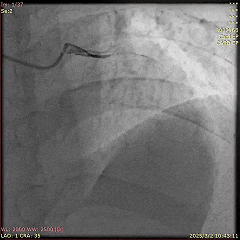

冠脉造影示:冠状动脉弥漫性粥样硬化斑块,左前降支(LAD)次全闭塞,回旋支(LCx)中段存在一处模糊病变,TIMI血流接近正常3级,右冠状动脉为LAD提供侧支循环(Rentrop 3级)。

首次PCI的冠脉造影